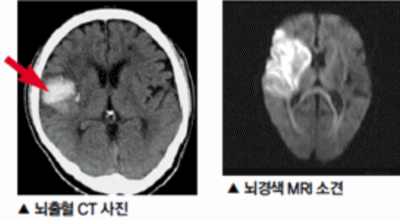

뇌 속에 혈액을 제공하는 혈관이 있는데, 이 혈관이 막히면 정상적으로 지급되어야 할 만큼의 혈액이 뇌까지 도달하지 못하여 뇌조직이 제 역할을 수행하지 못하는 것을 말해요. 이 시간이 지속될 경우 몸의 여러 곳에 지장이 생기며 이것을 뇌경색이라고 해요.

뇌경색이 생기는 원인은 아주 다양해요. 뇌경색은 뇌의 혈관이 막혀 뇌의 일부가 죽는 질병을 말하는데 주로 뇌경색의 원인은 혈전이며, 혈전으로 인해 뇌혈관이 막히는 위험 인자는 혈전을 발생하게 해요. 또한 동맥경화나 심장병, 혈관박리, 뇌혈관 기형 등으로 말미암아 생기게 될 수 있다고 하며 대부분이 60세 이상의 고령층에서 빈번히 나타나는 질환으로 알려져 있답니다.

뇌경색 증상이 처음 나타난 후 4-5시간이 경과하지 않았다면 주사 제제를 통한 혈전용해술을 시도해 볼 수 있어요. 24시간이 경과하지 않았고 대뇌혈관이 막힌 것을 확인하였다면 막힌 혈관에 대하여 기계적 재개통술을 시도할 수 있어요.